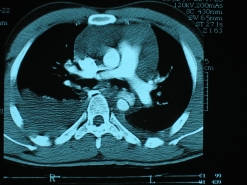

Η αξονική αγγειογραφία επιτρέπει τη διάγνωση και παρέχει πληροφορίες για τις διαμέτρους της αορτής, την ύπαρξη συλλογής, την επέκταση του διαχωρισμού. Δίνει επίσης πολύτιμες πληροφορίες για την άρδευση των ζωτικών οργάνων.

Το διοισοφάγειο υπερηχογράφημα είναι μια εξέταση που εκτός από τη διάγνωση και τη διάμετρο της αορτής, δίνει πληροφορίες για την αορτική βαλβιδική λειτουργία και τη λειτουργία της αριστερής κοιλίας.